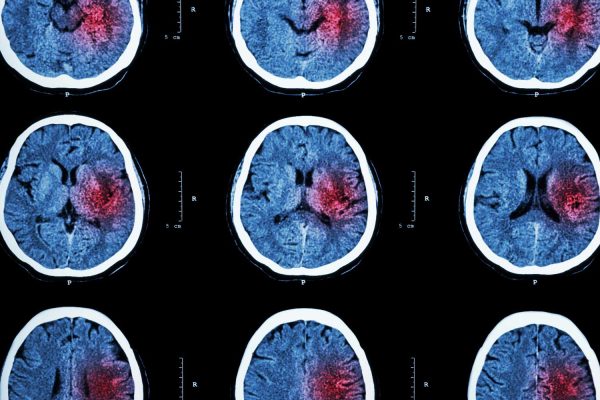

When your doctor orders advanced imaging, you may hear the terms MRI and MRA — and while they sound similar, each serves a specific purpose in diagnosing health conditions. Understanding the difference can help you feel more confident and informed about your care.